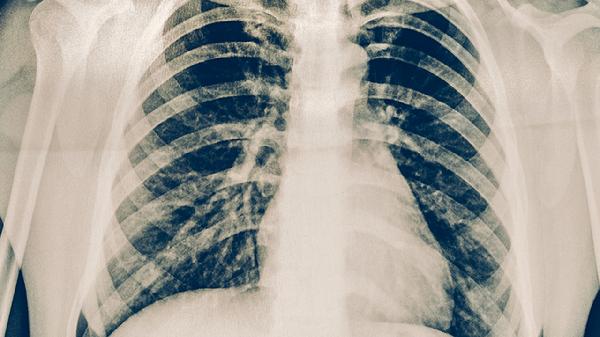

肺結(jié)核患者需注意隔離防護(hù)、規(guī)范用藥、營養(yǎng)支持、定期復(fù)查及癥狀監(jiān)測。肺結(jié)核是由結(jié)核分枝桿菌引起的慢性傳染病,主要通過呼吸道傳播,患者應(yīng)嚴(yán)格遵循醫(yī)囑并做好日常管理。

治療初期每月需進(jìn)行痰涂片檢查,后期每2-3個(gè)月復(fù)查胸部CT。用藥2月末應(yīng)評估痰菌轉(zhuǎn)陰情況,全程治療結(jié)束需隨訪2年。出現(xiàn)咯血、持續(xù)低熱等異常需提前復(fù)診。